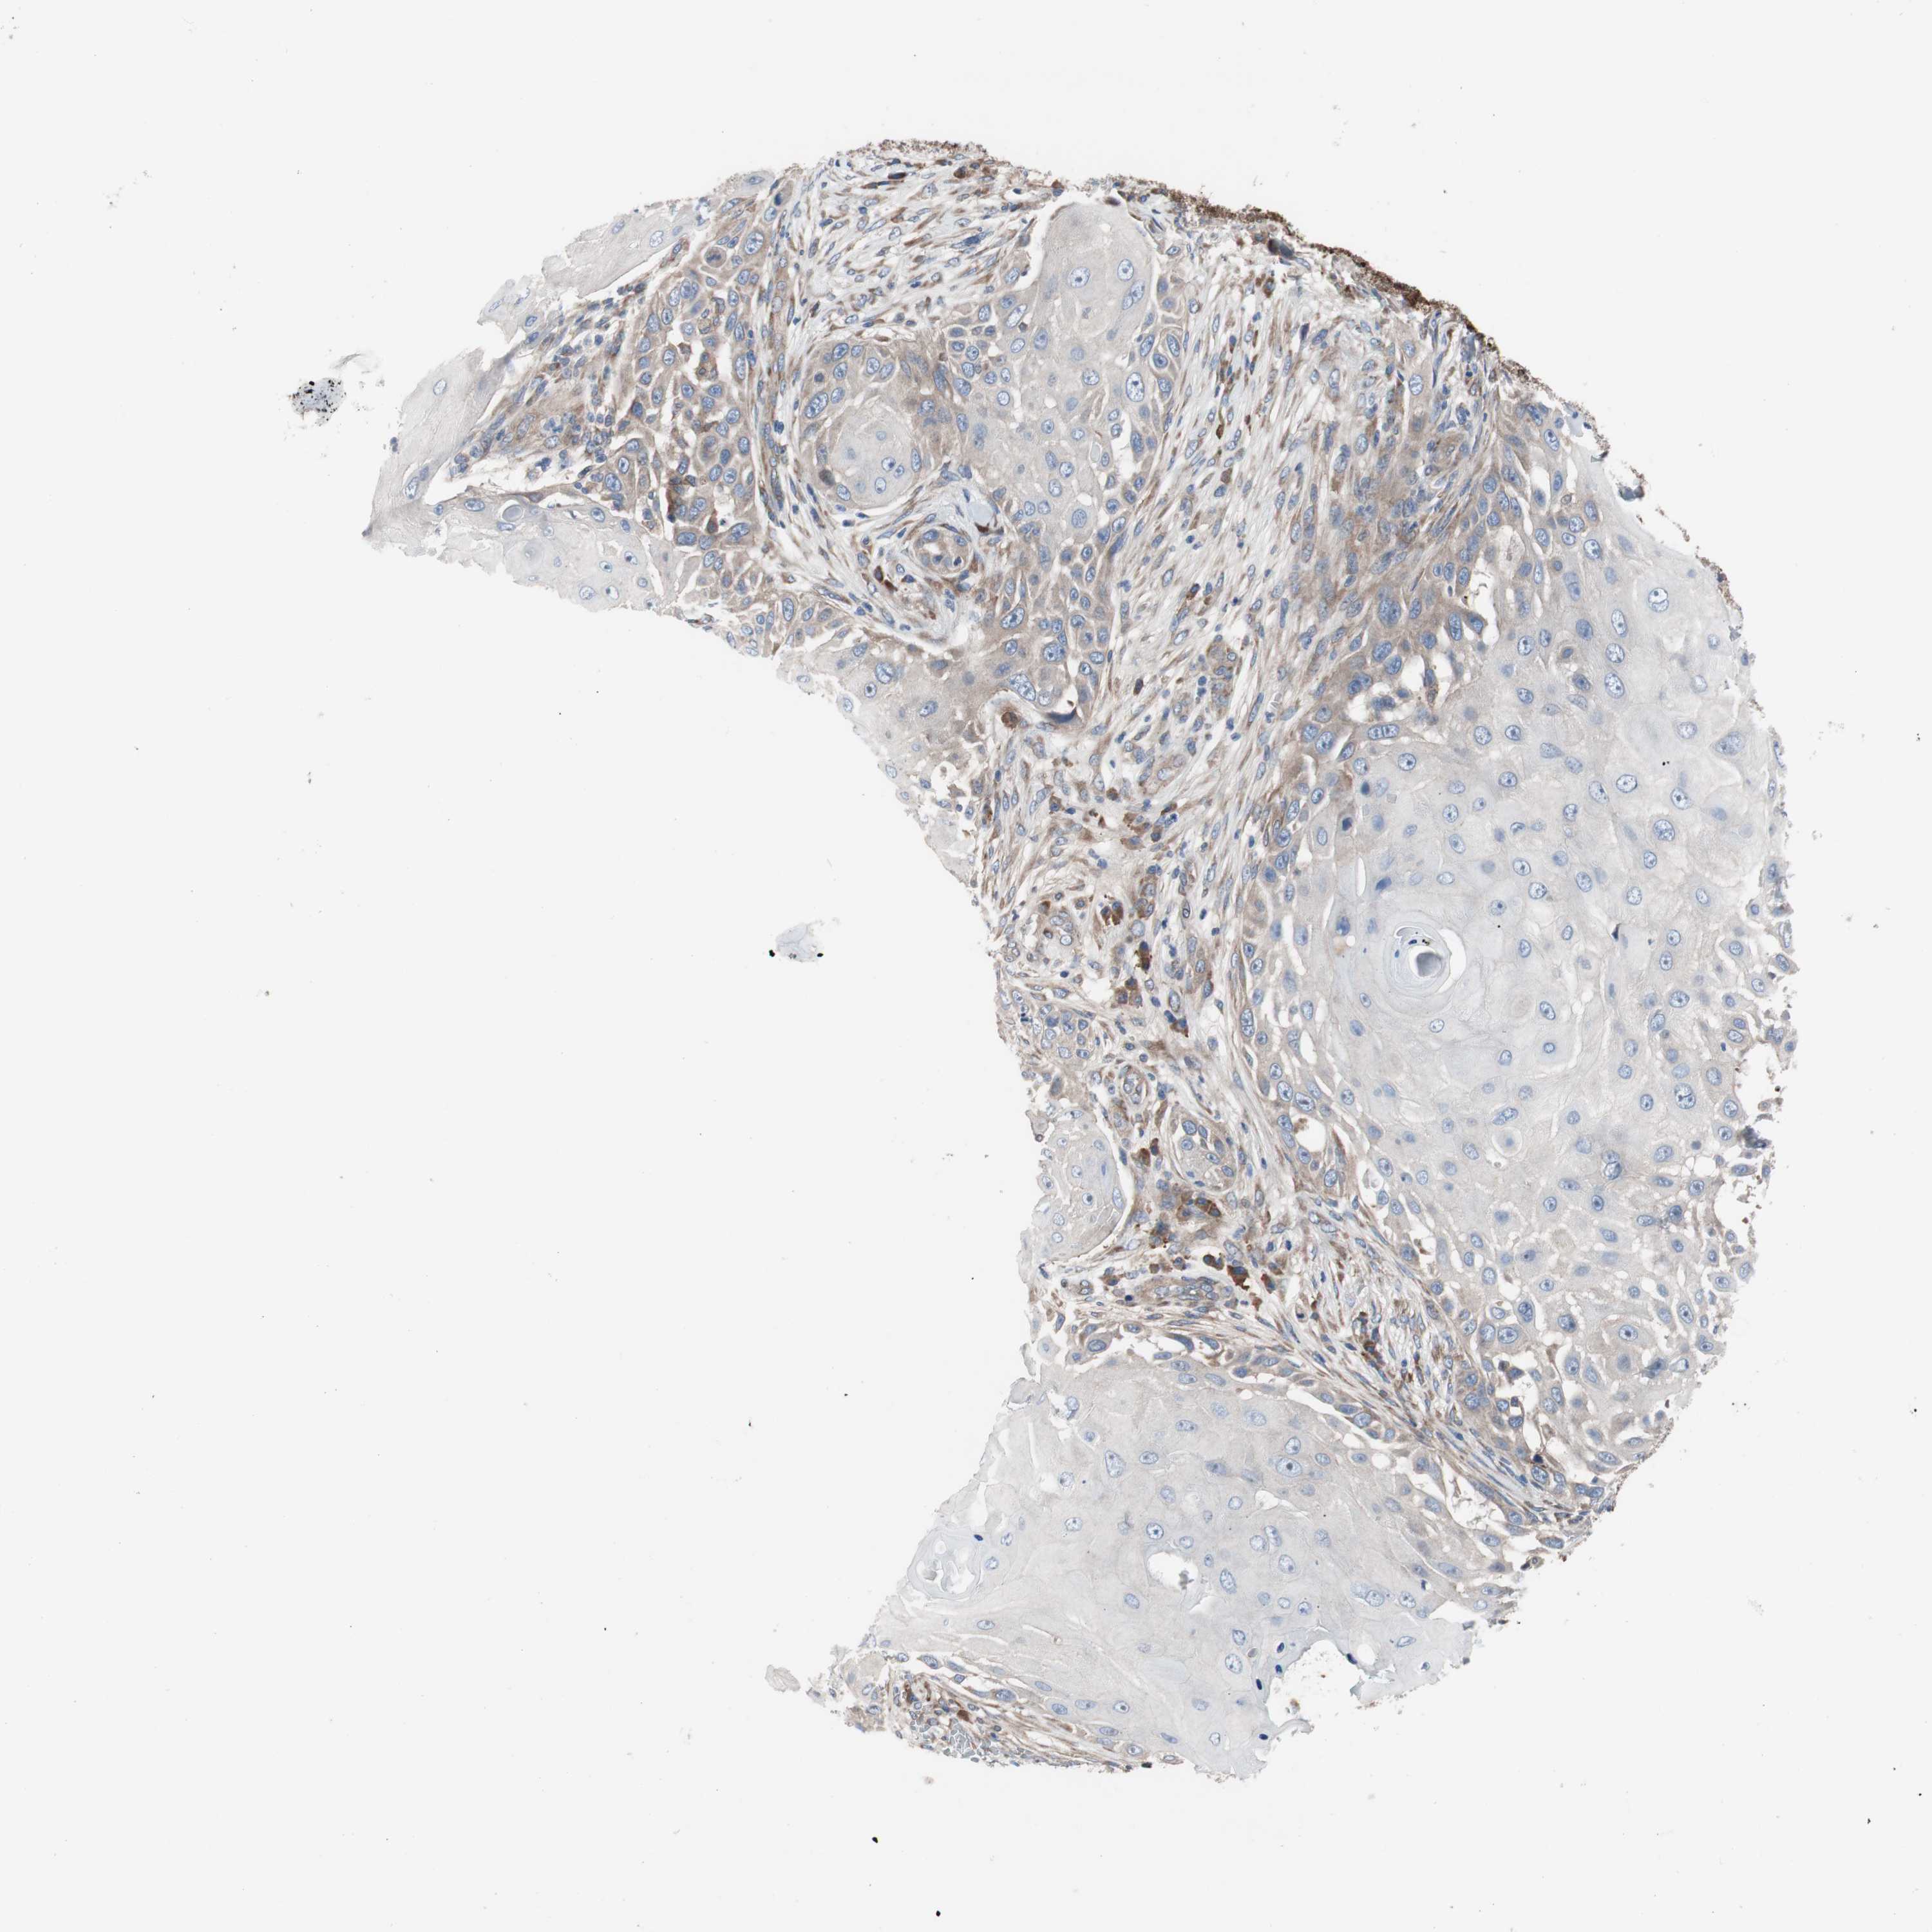

SKIN CANCER - Protein expressioni

A mouse-over function shows sample information and annotation data. Click on an image to view it in a full screen mode. Samples can be filtered based on level of antibody staining by selecting one or several of the following categories: high, medium, low and not detected. The assay and annotation is described here.

Each image is clickable and will lead to virtual microscopy that enables deeper exploration of all samples and also displays staining intensity scores, fraction scores and subcellular localization as well as patient and tissue information for each sample.

Antibody HPA006874

Antibody HPA007208

Staining

High

Medium

Low

Not detected

Intensity

Strong

Moderate

Weak

Negative

Quantity

>75%

75%-25%

<25%

None

Location

Nuclear

Cytoplasmic/membranous

Cytoplasmic/membranous,nuclear

Squamous cell carcinoma, NOS

Basal cell carcinoma